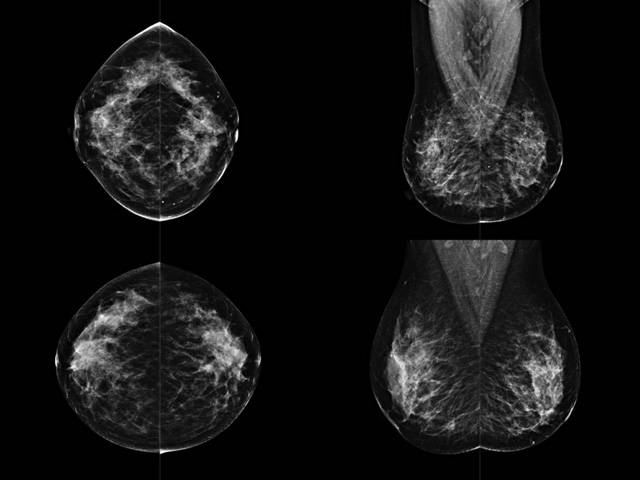

乳房检查时候要注意一些细节,需要更深入的了解这样才能使检查更准确。乳腺DR是乳腺癌的筛查诊断工具设备。是乳房方面检查的重要影像方法。它可以临床检查出早期的乳腺癌。可以判断良性恶性。因为它可以检查出早期的病变。对良性恶性检查的准确率达到90%以上。发病高峰年龄为45岁到54岁。50岁检查出来乳腺癌病患,可以让死亡率下降3成。所以30-40岁女性每年做一次乳腺DR检查。40岁以上就一年两次。如果家族史有乳腺癌的30岁以下也需要做检查。清晰显示乳腺各层组织严重的乳腺增生,乳腺炎,乳腺外伤也建议1年检查一次。极大提高了早期乳腺癌的敏感度和诊断率。

大角度、高质量的乳腺检查,可以让女性带来身体健康安全。为医生提供了高清影像数据。乳腺检查时候各个部位影像显示出来。白色乳腺导管跟纤维结缔组织。模糊的是脂肪。病变一般是不透明的白色。有需要放大来检查。乳腺DR没有重叠伪影。辐射剂量更少。因为乳腺癌发病每年都有所提高,对女性都造成了严重的身体健康危害。早做检查早治疗是不可忽视的举措。可以大大的降低死亡率。保证身体健康。一般检查避开经期,来完7天左右是最佳的检查时间。绝经的女性就没有要求。孕妇不参加乳腺DR检查, 6个月内准备妊娠的妇女也不宜行此检查。